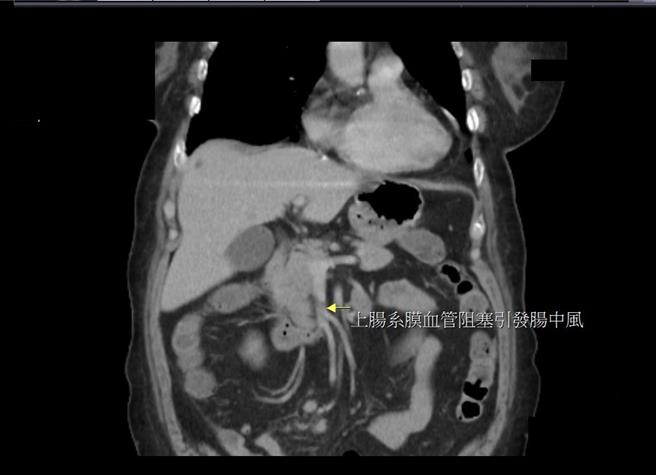

大千综合医院外科部主任冯启彦表示,一般民眾较熟知脑中风或心肌梗塞,但对于肠中风较陌生,其实肠中风与脑中风、心肌梗塞形成的原因是一样的,都是血管阻塞产生的缺氧坏死,常出现在糖尿病及高血压的病人身上。肠中风容易发生在上肠系膜动脉阻塞,而上肠系膜动脉供应大多数小肠及一部份大肠的血流,因此一旦发生血管阻塞,影响的肠道非常广泛。

冯启彦说明,发生肠中风时,若延误太久导致肠道坏死,往往需要将大部分的小肠全部切除,病人会因短肠症造成营养不良及高死亡率。此次个案幸好发现得早,经由通血路药物、给足水份及高浓度氧气之后,肠道坏死现象有逐渐改善,一周后开始进食,并顺利出院返家。